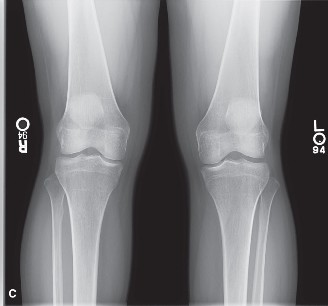

Initial plain radiographs of the left knee were obtained immediately post-injury:

*

Anteroposterior (AP), Lateral, Oblique, and Patellar Views:

* No acute fracture or dislocation was identified.

* Tibiofemoral and patellofemoral joint spaces appeared preserved.

* No osteochondral defects were visible on plain films.

Segond fracture:

Notably absent, which would suggest an avulsion fracture of the lateral tibial plateau associated with an ACL tear.

* Presence of a moderate joint effusion was confirmed.

* Subtle widening of the lateral compartment could be inferred due to valgus stress at the time of injury, but this was not conclusive for a significant chondral or osseous injury on plain films.

*Figure 1: Lateral radiograph of the left knee demonstrating a moderate joint effusion (patellar fat pad effacement and suprapatellar pouch distension) with no obvious acute fracture or dislocation. Osseous alignment is preserved. This view helps rule out gross bony pathology.*